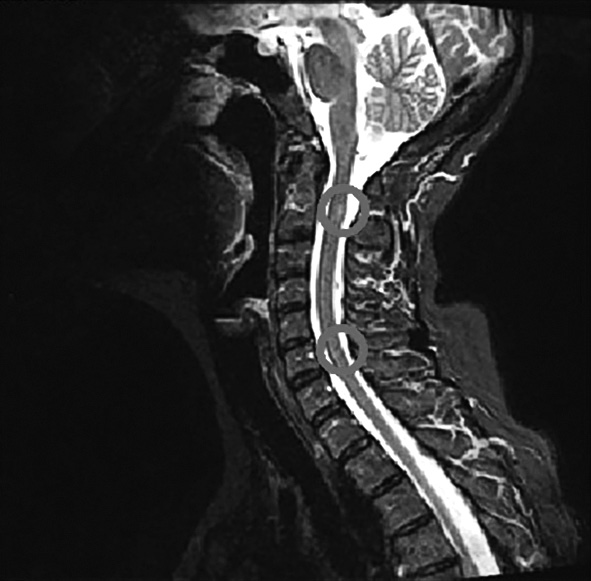

13.03.2019 выполнена МРТ шейного отдела позвоночника с контрастированием. В веществе спинного мозга на уровне зубовидного отростка С2 визуализируется очаг гиперинтенсивного по Т2 сигнала, без чётких контуров, размерами 0,5 × 0,4 × 0,5 см. Аналогичный очаг имеется на уровне С5/С6, размерами 0,3 × 0,2 × 0,3 см. На других уровнях спинной мозг структурен, сигнал от него (по Т1 и Т2 не изменен). Форма и размеры тел остальных позвонков обычные, интенсивность сигнала костного мозга тел позвонков не изменена (рис. 2).

Рис. 2. МРТ шейного отдела позвоночника пациентки С. в режимe STIR от 13.03.2019. / Fig. 2. Cervical spine MRI of patient S. — STIR sequence, 13.03.2019.